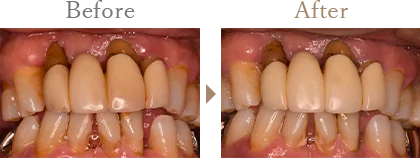

THPの症例

| 主訴 | 健康な細菌叢の獲得・維持を希望 |

|---|---|

| 年齢 | 60代 |

| 性別 | 男性 |

| 治療内容 | 左上歯ぐきが腫れていて、歯もぐらぐらする。歯周病治療をしたいと当院に来院され、トータルヘルスプログラムを実施。 |

| 治療期間 | 53日 |

| 治療費 | 195,800円(税込) |

| リスク | 健康な細菌叢を維持するために、 定期予防メインテナンスが推奨される。 |

| 担当DH | DH 霜島 |

| 年齢 | 30代 |

| 性別 | 女性 |

| 治療内容 | 初心検査時には歯周ポケット4mm以上が17%あり、BOPは47%、上顎前歯は動揺度Ⅱの箇所もあり、位相差顕微鏡像では活動性の高い歯周病菌が確認できます。 |

| 治療期間 | 64日 |

| 治療費 | 184,800円(税込) |

| 担当DH | DH 佐々木 |